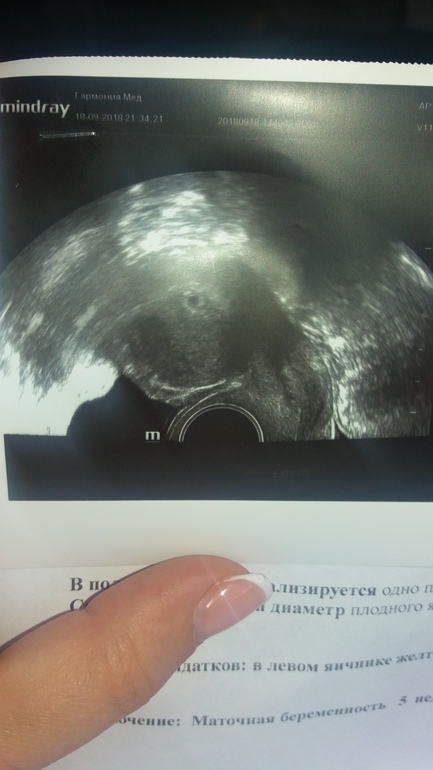

Узи🤗🌹

Сегодня была на приёме,боялась очень..но доктор меня успокоила)все хорошо🙂на 8й неделе нужно вставать на учет📆